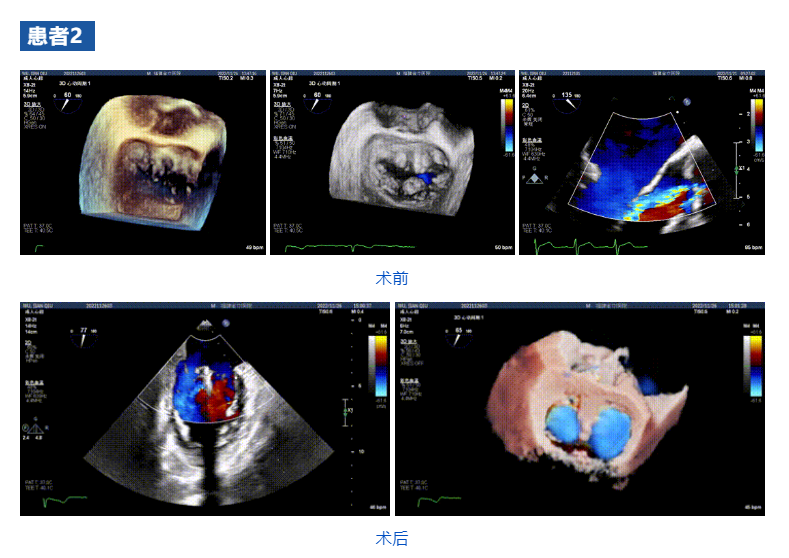

接受治療的三例患者均為器質(zhì)性重度二尖瓣反流(DMR)患者,術(shù)前超聲提示二尖瓣后葉脫垂伴4+反流,左室舒張功能減退。郭延松教授攜同團(tuán)隊(duì)成員陳新敬副教授和洪景宣、方明程、楊清勇主治醫(yī)師、心外科丁杭主任以及超聲科賴寶春、葉振盛主治醫(yī)師共同進(jìn)行病情討論??紤]到患者高齡、基礎(chǔ)疾病多、STS評(píng)分高,為外科手術(shù)極高危患者,不適合進(jìn)行外科開胸二尖瓣手術(shù),因此決定為患者實(shí)施經(jīng)導(dǎo)管緣對(duì)緣修復(fù)介入術(shù)(JensClip經(jīng)導(dǎo)管瓣膜夾系統(tǒng))。

在浙江大學(xué)醫(yī)學(xué)院附屬第二醫(yī)院王建安教授團(tuán)隊(duì)的支持下,手術(shù)經(jīng)股靜脈-房間隔入路,采用全身麻醉插管,在TEE和DSA引導(dǎo)下完成房間隔穿刺。置入JensClip瓣膜夾系統(tǒng)后,在左房調(diào)整瓣膜夾的位置和軸向,后進(jìn)入左室,在TEE引導(dǎo)下捕捉二尖瓣前后瓣葉,并關(guān)閉瓣膜夾。經(jīng)TEE反復(fù)確認(rèn)手術(shù)效果后最終鎖定并釋放瓣膜夾。術(shù)后即刻超聲顯示瓣膜夾位置穩(wěn)定,功能良好,二尖瓣反流由術(shù)前4+減少至微量,手術(shù)圓滿成功。